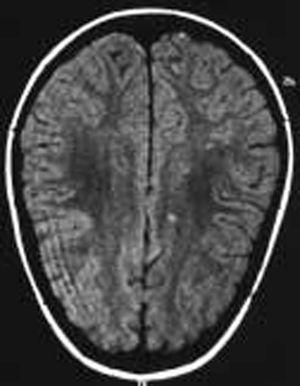

Paciente varón de 11 años de edad sin antecedentes personales de interés remitido desde atención primaria por un cuadro clínico agudo de cefalea y visión borrosa. En el momento de la consulta el paciente se encontraba asintomático. Refería cefalea habitual que en el último mes había aumentado de intensidad y periodicidad, de características pulsátil, localización bitemporal, predominio matutino, que aumentaba con los movimientos de la cabeza y que cedían con analgesia habitual. Se acompañaba de anorexia, pérdida ponderal, labilidad emocional y visión borrosa de manera intermitente. Como antecedentes familiares de interés destacaban numerosos diagnósticos de migraña en la rama materna. La exploración física y neurológica detallada fueron normales. Se le realizó examen de fondo de ojo donde destacaba una discreta palidez de ambas papilas del nervio óptico. Se le practicó una TC, que fue normal, y una punción lumbar que objetivó una presión de apertura de 360 mmH2O, con citoquímica y bioquímica normal. El cultivo y el estudio viral en LCR resultaron estériles. En la RM cerebral se apreciaron pequeñas alteraciones puntiformes de aumento de señal en sustancia blanca subcortical de ambos lóbulos frontales y temporal derecha en densidad protónica y en secuencia T2 (fig. 1). La resonancia por angiografía fue normal. La agudeza visual estaba disminuida (ojo derecho, 0,7, y ojo izquierdo, 0,8) y en la campimetría se apreciaba una pérdida visual bilateral (ojo izquierdo 14/120; ojo derecho 22/120). Los potenciales visuales evocados manifestaban retraso de latencia en la vía óptica, sobre todo izquierda. El estudio de autoinmunidad fue normal. El estudio de hipercoagulabilidad reflejó un estado de heterocigosis para el factor V de Leiden con una resistencia para la proteína C (ratio): 1,87 (normal: 2-5). El estudio familiar desveló el estado de heterocigosis del padre con una resistencia a la proteína C (ratio): 1,65 (normal: 2-5).

Figura 1.Caso 1. Lesiones hiperintensas puntiformes sugerentes de microinfartos.

Se sugiere que los microtrombos de la vellosidades aracnoideas dificultaría la reabsorción del LCR. La trombosis de los pequeños vasos cerebrales, la agresión isquémica y el daño microvascular aparecen como la explicación fisiopatológica a la asociación de HIB y los estados de hipercoagulabilidad 7. En nuestros pacientes no hemos encontrado evidencia de lesión del árbol cerebrovascular; sin embargo, las lesiones difusas inespecíficas en secuencias T2 en la sustancia blanca podrían sugerir microinfartos vasculares cerebrales.